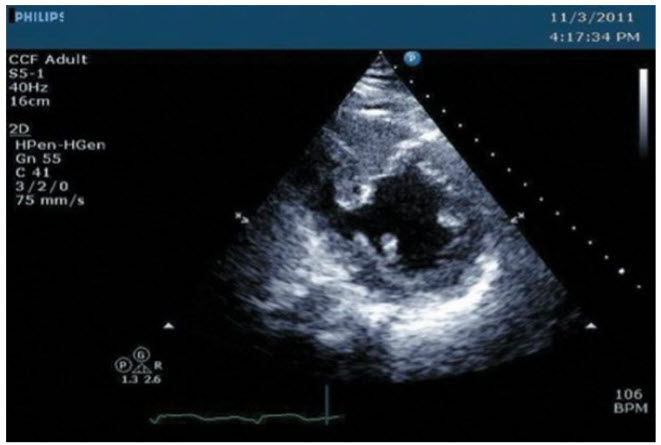

A 75-year-old woman presented with shortness of breath and generalized malaise of 1-week duration. Her heart rate was 90 per minute and BP was 90/50 mmHg. Examination revealed rales in bilateral lung bases, an elevated jugular venous pulse, and a loud systolic murmur in the left parasternal area. An echo (Fig. below) was performed.

Mid RCA in dominant RCA. The echo shows a VSR in the basal inferoseptum. This area is usually supplied by the PDA. As a result, a dominant RCA infarction likely accounts for these changes.